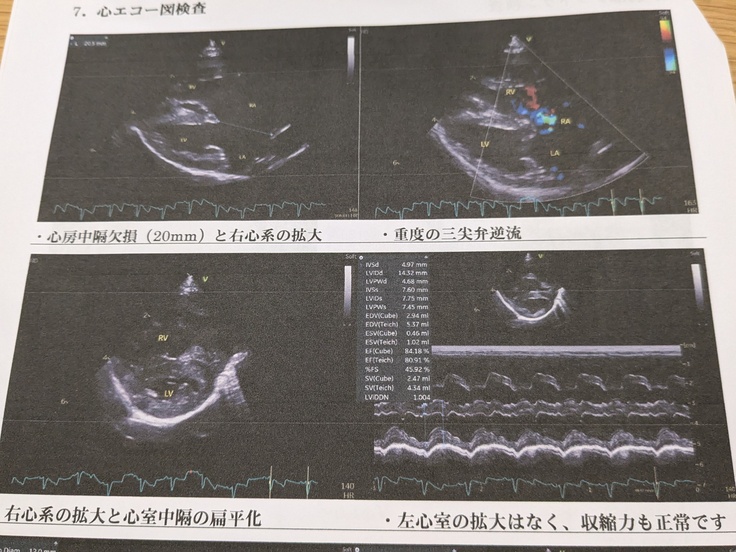

“心雑音”を確認したことから、詳しく調べるため【エコー検査】を実施。

すると、心臓内の4つある部屋(右心房、右心室、左心房、左心室)を隔てる壁が1つ無いかもしれないことが判明。

10月9日受診、各種検査の結果『不完全型房室中隔欠損症』いわゆる、部屋を分ける壁がない。(通常壁に2mm空いているだけで手術が必要とのことであらが、2cmにもなる穴が空いているとのこと)

検査の結果。

▶以前の病院同様「不完全型房室中隔欠損症」であるとのこと。

▶心拡大が進行しており、重度な三尖弁逆流もあるため早急な外科治療が必要とのこと。

※セカンドオピニオン結果

※心拡大を確認

※エコー検査結果

※写真の赤マル内の中隔が無い(2センチにもなる穴がある)